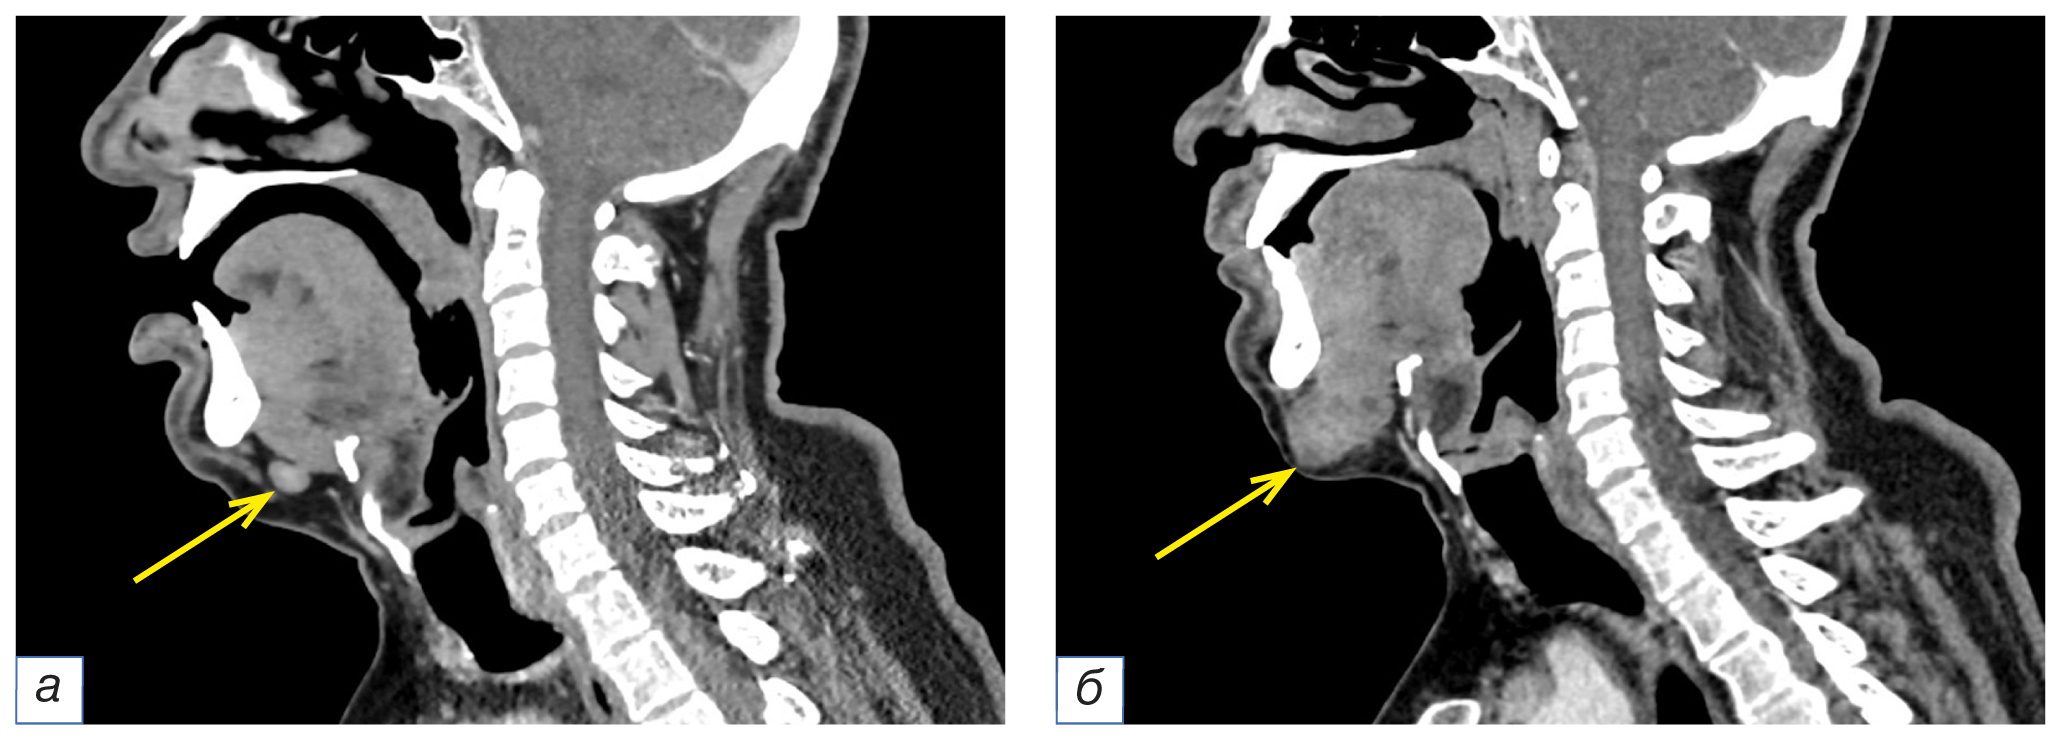

В 4 (6,5%) случаях в мягких тканях шеи не были описаны изменённые лимфатические узлы подбородочной области (группа Ia) и нижние ярёмные (группа IV). Все они были округлой формы размером от 10 до 14 мм, неоднородной структуры, слабоинтенсивно негомогенно накапливали контрастный препарат (рис. 5).

Рис. 5. Фрагменты компьютерных томограмм области головы и шеи в сагиттальной плоскости (а, б). У пациента в возрасте 63 лет с диагнозом рака красной каймы нижней губы рT3N0M0 определяется округлой формы подбородочный лимфоузел (группа Ia) с чёткими ровными контурами, неоднородно накапливающий контрастный препарат, размером до 11×9 мм (а, жёлтая стрелка). На контрольном исследовании через 3 месяца отмечается увеличение вышеописанного лимфоузла до 33×24 мм (б, жёлтая стрелка).

Fig. 5. Computed tomograms of the head and neck, sagittal planes (а, б). A 63-year-old patient with cancer of the red border of the lower lip pT3N0M0 has a round-shaped submental lymph node (group Ia) with clear, even contours, heterogeneously accumulating the contrast agent, measuring up to 11×9 mm (а, yellow arrow). A control study after 3 months showed the enlargement of the above-described lymph node to 33×24 mm (б, yellow arrow).